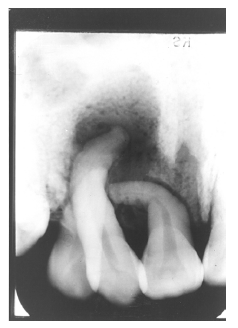

Figure 7 - Extensive Loss of Alveolar Bone

Figure 7 illustrates severe periodontal disease with extensive loss of alveolar bone around the tooth.